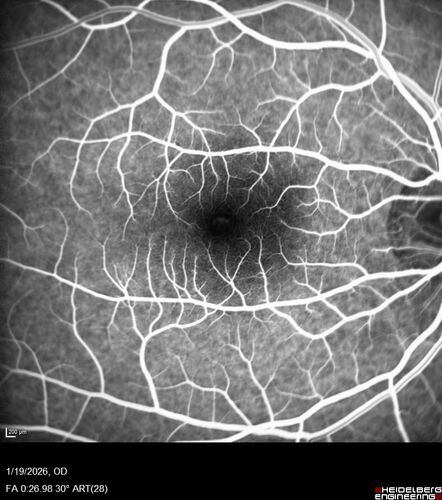

Acute Retinal Pigment Epitheliitis (Krills disease)

15 year old with sudden central vision loss in one eye. The vision loss persisted though for at least 6 months (which may be a laser injury)